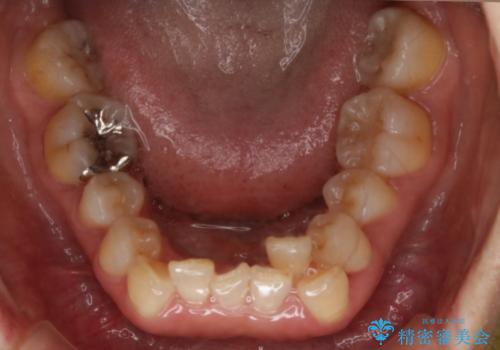

- 上下の歯のがたつきと、噛み合わせが深いことを気にされてご相談にいらした方です。噛み合わせに参加していない歯を抜歯してインビザラインにて治療を行いました。

一般的に噛み合わせの深い方へのインビザライン治療は適応が難しいとされていますが、今回は噛む力を上手にコントロールできたことと、内側に入り込んでいた前歯の角度を調整したことで下の歯がしっかり見えるようになりました。短期間で劇的に見た目が改善し、大変喜んでいただけました。